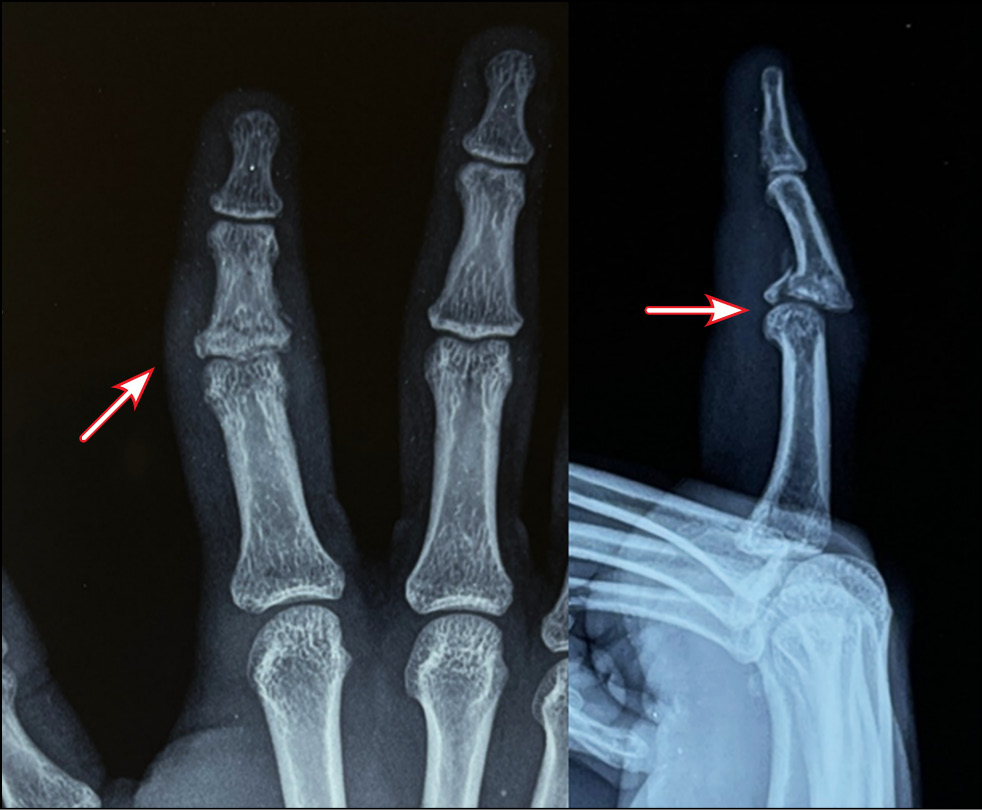

All patients underwent preoperative diagnostics: radiography, computed tomographic study, and clinical evaluation of the range of motion in the joint. According to the radiological and tomographic signs, the fractures of the palmar edge of the base of the middle phalanx with its dorsal subluxation, and in three cases fractures of the dorsal edge of the base of the middle phalanx with palmar subluxation, accompanied by failure of the central bundle of the tendon of the common extensor tendon of the finger, were determined as malunion fractures. According to the Eaton classification, they are categorized as groups IIIa and IIIb. In all cases, the amplitude of movements in PIP joints was sharply limited; flexion was up to 30°. Pain syndrome at the moment of attempted flexion in the joint was assessed by patients ranging from three to four points on VAS.

Fig. 14. Appearance and X-ray picture.

Fig. 15. Marking of computed tomography.